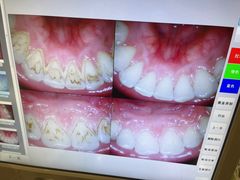

• 牙易美口腔(圣堂店)

• -牙易美口腔(圣堂店)